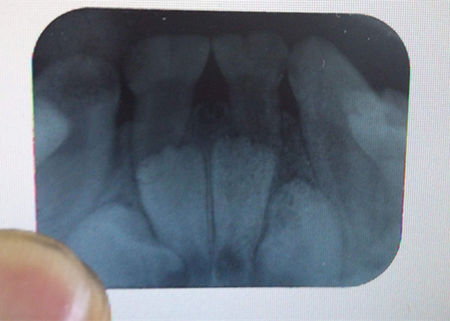

1)X線牙片

X線牙片(dental film)又稱(chēng)根尖片,臨床常用的牙影像檢查方法,主要顯示牙體,牙髓腔、根管及根尖組織。牙片大小為3cmx4cm,一張牙片可了解1-3顆牙的詳細(xì)情況。